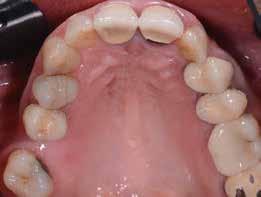

A rendelésünkön jelentkező 40 éves nőbeteg a mosolyának esztétikai megjelenésén szeretett volna javítani (1. ábra)

A vizsgálat során a jobb felső első kisőrlőfog (1,4) és a bal felső első kisőrlőfog (2.4), valamint a köztük elhelyezkedő fogak kifejezett mértékű kopását észleltük (14-24). Ezen felül a felső metszőfogak (1.2–2.2) élei egyenetlen lefutással rendelkeztek, és a jobb felső nagymetszőfog (11) – amelyet korábban gyökérkezeltek és kompozit töméssel láttak el –jelentős színbeli eltérést mutatott. Az 1.4-es és 2.4-es fo-

A belső fogfehérítés utáni állapot.

gak között mért tasakmélység mértéke sehol sem haladta meg a 3 mm-t. A páciens számára belső fogfehérítést, ínyplasztikát és kerámia héjak készítését javasoltuk. A páciens a felajánlott kezelési tervet elfogadta. Első lépésként az 1.1es fog belső fogfehérítését terveztük, mivel a későbbiekben ezt a fogat is kerámia héjjal akartuk ellátni.

A páciens elégedett volt a végleges restaurátumok színével, formájával és méretével. A kezelés végeredménye kielégítette az esztétikai elvárásait (9. ábra). A frissen átadott restaurátumok épségének megőrzése érdekében a páciens számára éjszakai fogvédősínt készítettünk. A páciensünk a négyéves kontrollvizsgálat során is nagyon elégedett volt a kezelés eredményével. A korábban meglévő fekete háromszögek eltűnésének különösképpen örült (9. és 10. ábrák)